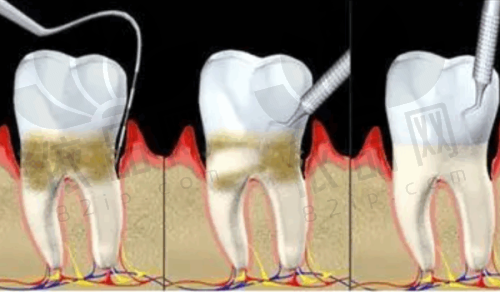

一家连锁口腔所属商圈为中山路,是连锁口腔医院。院内实行24小时电话预约制度,开设有晚班,患者可提前预约,无需等待直接就诊。院内还贴心为患者准备了免费的茶水、WIFI、儿童游乐区、VIP等候休息区等。它是国内连锁的品牌,在多个城市都有连锁店,除了乌鲁木齐天山区和水磨沟区有两家外,西安、咸阳、宝鸡等城市也有特别多家。其全称是一家连锁口腔中山路门诊部,审批机关是乌鲁木齐市天山区卫生健康委员会,登记号为6501020097,诊疗项目包括口腔科、牙体牙髓病、牙周病、口腔粘膜病、儿童口腔、口腔颌面外科、口腔修复、口腔正畸、口腔种植、口腔麻醉、口腔颌面医学影像、预防口腔,还有医学检验科的临床体液、血等。